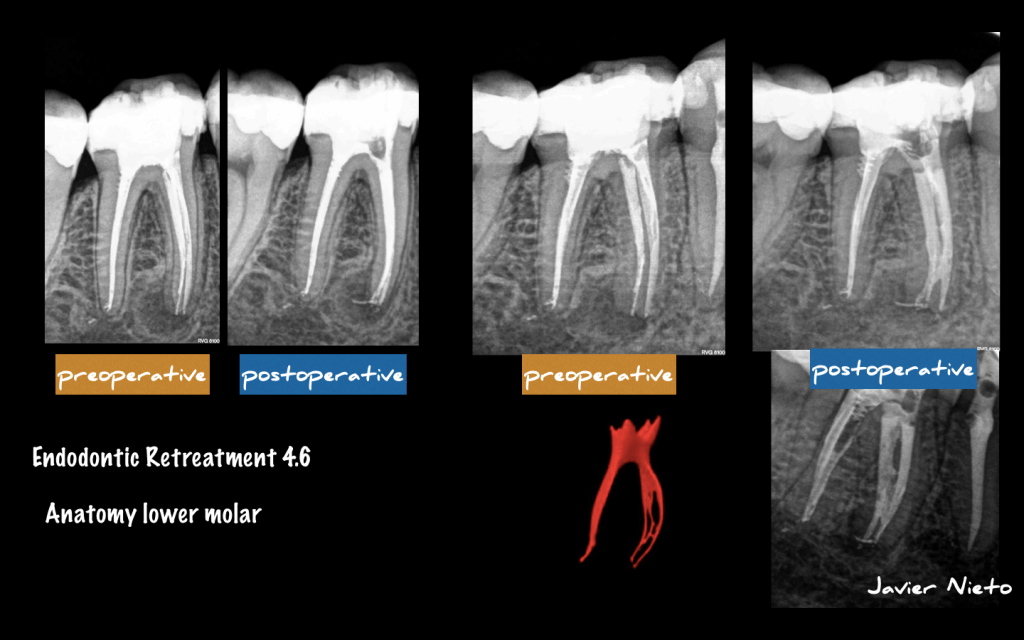

Retratamiento de un 4.6

Paciente que acude a nuestra consulta para valorar un tratamiento de endodoncia realizado hace 6 meses, motivo, quieren exodonciarlo (EXTRAERLO) ya que según el operador, «hay veces que la endodoncia fracasa» .

Evaluamos el caso y decidimos retrartarlo, ya que pensamos que existe una subobturación.

Como conocemos la gran variabilidad anatómica de las raíces mesiales de los molares inferiores, sospechamos del itsmo de unión.

Nuestro empeño irá encaminado a limpiar ese istmo.

Finalmente, un caso con muy buen pronóstico.